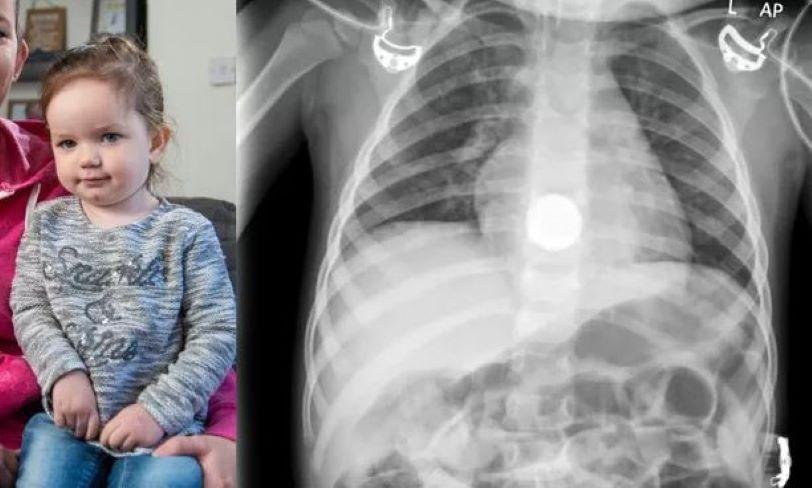

Un copil de 2 ani a înghițit o baterie și a ajuns la spital. Cazul a avut loc zilele trecute în orașul Krasnogorsk din Rusia.

După cum au spus părinții, copilul a înghițit din greșeală o baterie rotundă. Mama și tata îngrijorați au încercat mai întâi să îndepărteze singuri obiectul străin, dar fără rezultat. Părinții au așteptat că bateria să iasă singură din tractul intenstinal, însă aceasta nu s-a întâmplat, deoarece obiectul s-a blocat în esofag.

Copilul a fost internat de urgență, când a început să respire anormal și să saliveze abundent. Medicii au început să o examineze pe fată și au aflat că bateria înghițită era blocată în esofag.

„Datorită prezenței prelungite a bateriei în interiorul tractului gastrointestinal, fetița a dezvoltat necroză a peretelui esofagian. Este important ca părinții să știe: dacă un copil a înghițit un obiect străin, este necesar să se solicite imediat ajutor medical. Nu ar trebui să încercați să-l scoateți pe cont propriu sau să așteptați ca acesta să iasă singur”, spune medicul endoscopist Ivan Michurin, conform presei locale.

Sunt deosebit de periculoase bateriile care, la oxidare, pot provoca o arsură electrochimică și pot duce la consecințe ireversibile, până la perforarea peretelui esofagian.

Medicii au salvat copilul - bateria a fost scoasă prin metoda endoscopică. După operație, copilul a urmat tratament specializat.